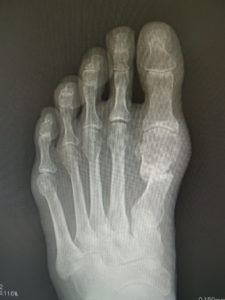

真田理事長による手術の様子。外反母趾|症例 (左から 手術前、手術後、ワイヤ抜去後)

60歳 男性